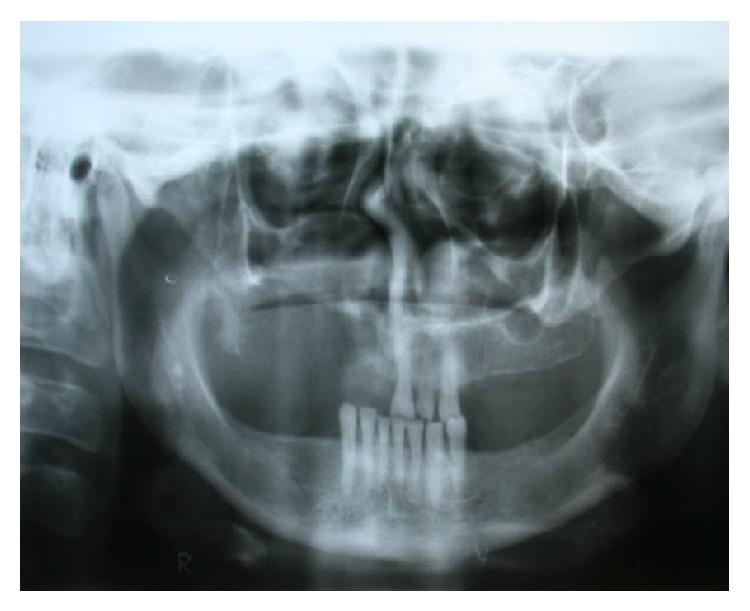

Adenoid cystic carcinoma is a cancer of the salivary gland that primarily affects the parotid, submandibular, and accessory salivary glands. Its growth is slow and it has infiltrative nature. A 46-year-old female patient coming from the rural area presented a lesion on the palate and reported pain in the region for three years. After incisional biopsy, and histopathological diagnosis of adenoid cystic carcinoma of the cribriform type of minor salivary gland, superior hemimaxillectomy and adjuvant treatment with radiotherapy and maxillofacial prosthetic rehabilitation were performed.

腺样囊性癌是一种主要影响腮腺、颌下腺及副唾液腺的唾液腺癌。其生长缓慢且具有浸润性。一名来自农村地区的46岁女性患者腭部出现肿物,该区域疼痛三年。经切开活检,组织病理学诊断为小唾液腺筛状型腺样囊性癌,遂行上颌骨次全切除术,并进行放疗及颌面修复辅助治疗。